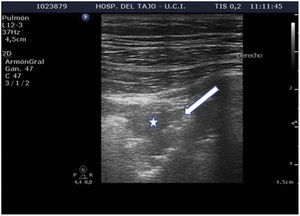

Subpleural condensationsSubpleural condensations appear as hypoechoic zones with poorly defined margins in contact with the pleura (Fig. 6), and usually are no larger than 1-2 cm in maximum diameter. They are generally found in the anterior zones of the thorax in patients in the supine position, and correspond to pulmonary inflammatory phenomena.

Alveolar consolidation or lung hepatization patternLung hepatization is described as a liver-like appearance of the consolidated lung seen at ultrasound exploration. This type of image is easier to visualize in supradiaphragmatic consolidations (Suppl. Fig. 6).